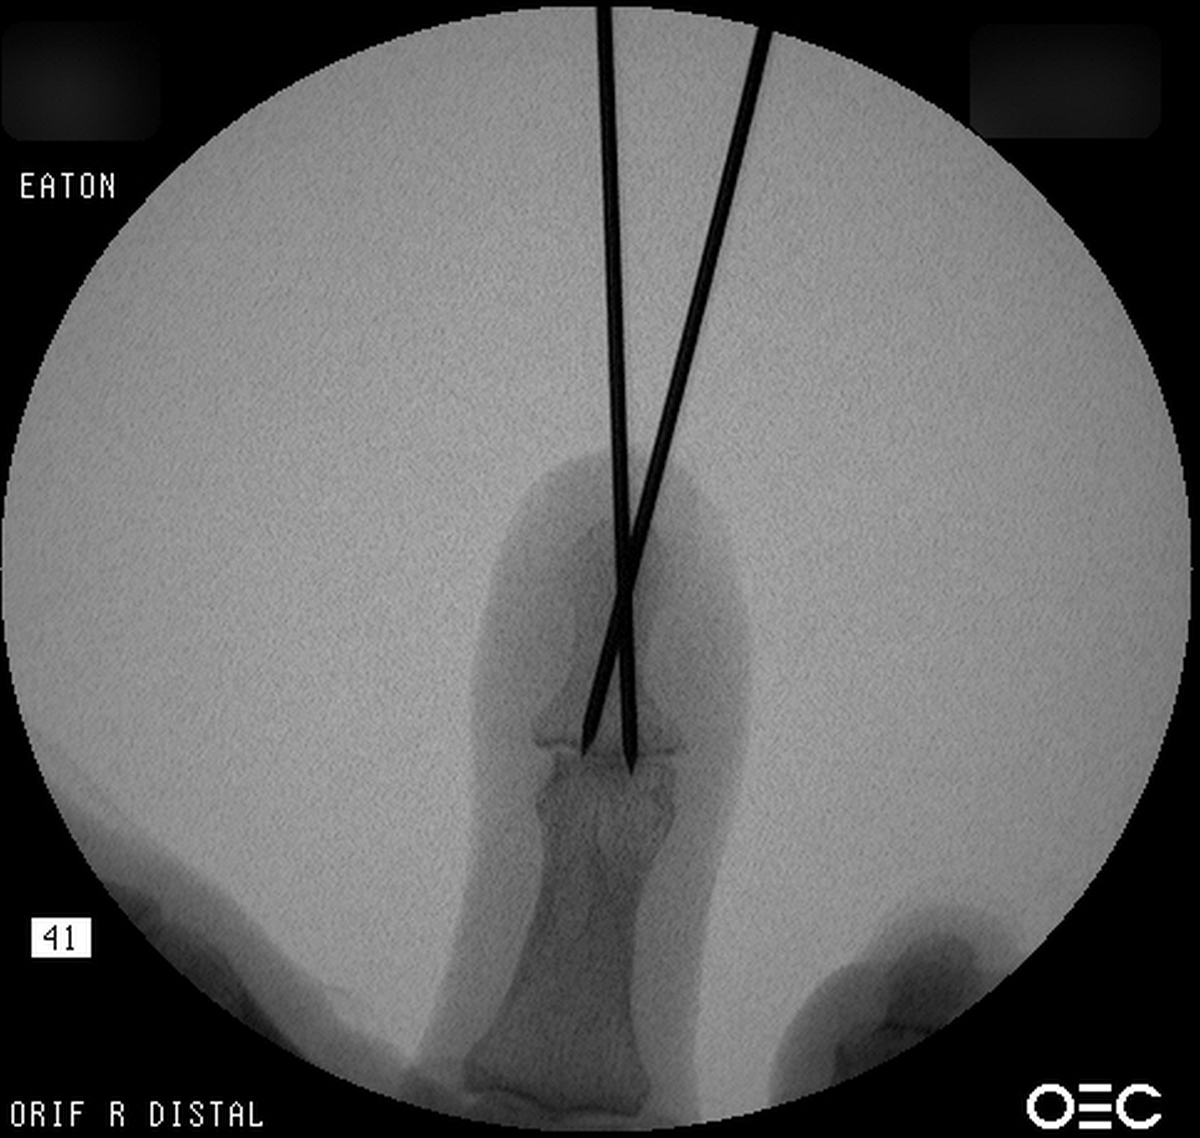

| Percutaneous

fracture stabilization with three pins via the

dorsal radial tubercle, radial styloid and FCR

portals. |